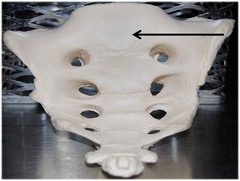

97

New cards

Coccyx

Name this specific bone.

98

New cards

Sacrum

Name this entire bone.